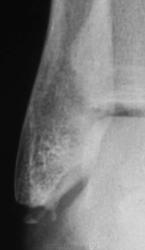

Травма. Пациент направлен на рентгенографию голеностопного сустава

Фрагментарный перелом наружной лодыжки, и ,кажеться, есть отрыв заднего бугорка таранной кости.

Классный перелом-филигранная работа, только верхушечка!

Отрывной перелом нижнего полюса наружной лодыжки. 3 недели в U-лонгете. Затем, даже если не срастается, то уже не болит, можно ходить далее. Перипроцесса не вижу, да и не знаю оного)